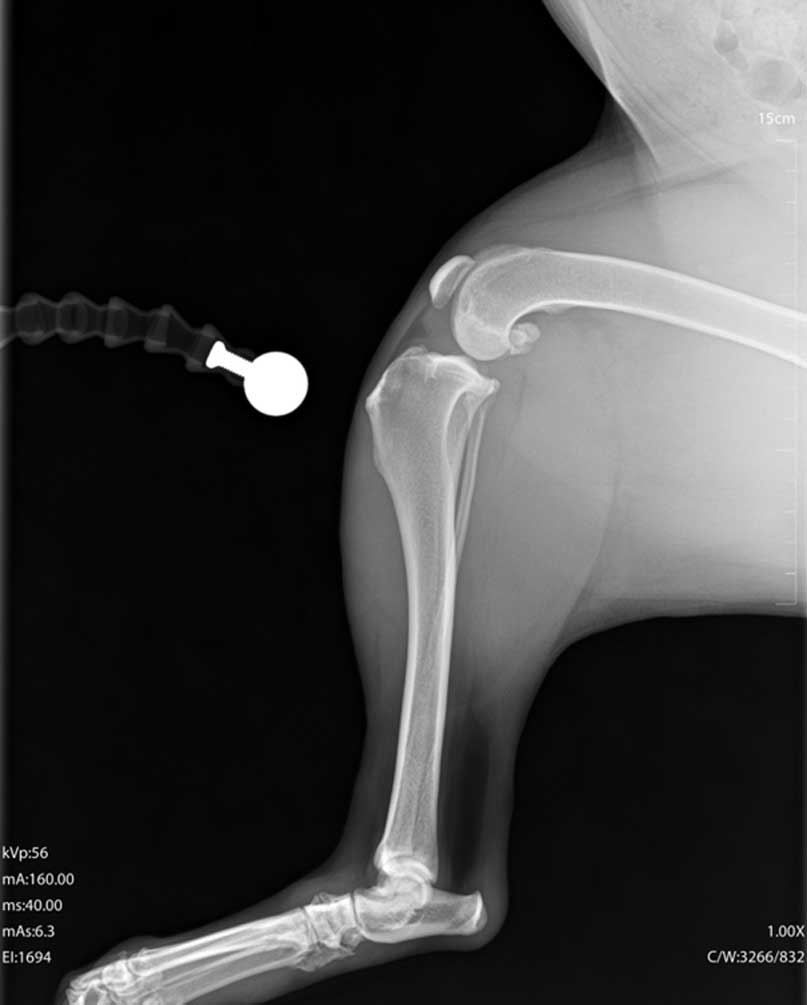

TPLO (Tibial Plateau Leveling Osteotomy) je kirurški zahvat koji se koristi za liječenje puknuća prednjeg križnog ligamenta koljena.

Tijekom TPLO operacije mijenja se kut gornje površine goljenične kosti kako bi se koljeno stabiliziralo bez potrebe za ligamentom.

Kirurg napravi kontrolirani rez na kosti, zakrene je u novi položaj i učvrsti posebnom metalnom pločicom i vijcima, time se sprječava klizanje potkoljenice pri opterećenju noge.

Većina pasa počinje opterećivati nogu unutar nekoliko dana nakon zahvata, potpuni oporavak traje otprilike 8 do 12 tjedana uz kontroliranu aktivnost i rehabilitaciju.

Prednost TPLO-a je brži i sigurniji povratak normalnom hodu, osobito kod srednjih i velikih pasa.

TPLO je danas jedna od najpouzdanijih i najčešće korištenih ortopedskih operacija u veterinarskoj medicini.